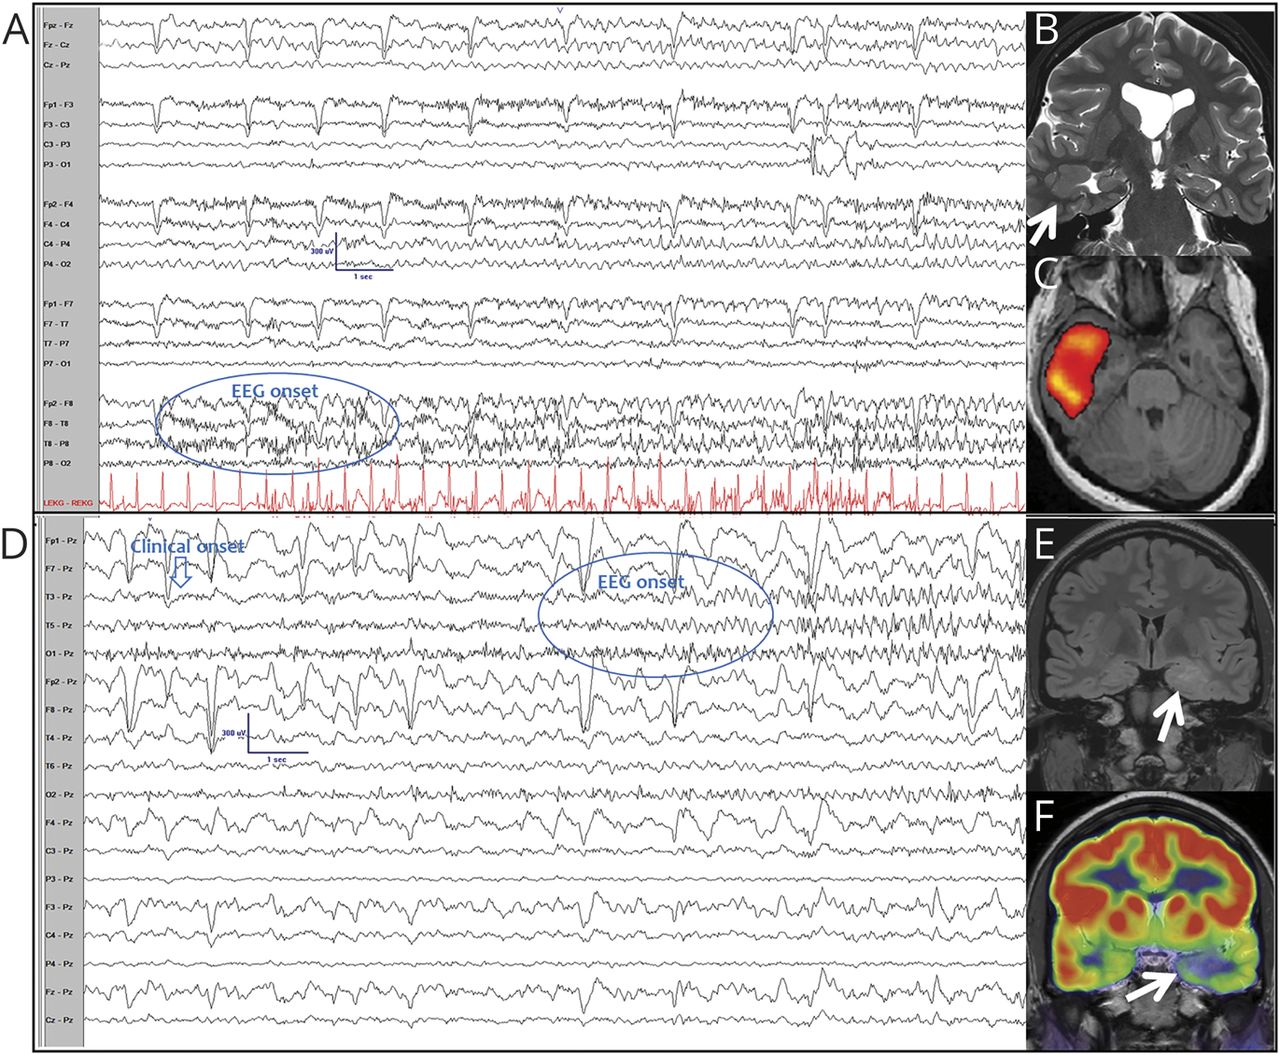

两个女人21岁和19年面对lesional耐药颞叶癫痫(框架)(表)与焦点意识受损癫痫(fia) (图)。住院视频脑电图监测捕获习惯性fia伴有同侧上肢的自动性,模仿一个指挥家管弦乐队(视频1)。

颞叶癫痫伴有同侧的自动性,模仿一个乐团的指挥家

(A)一个21岁的女人对temporal-onset癫痫临床发作(前脑电图出现(没有显示)。(B) t2加权MRI显示右颞皮质畸形。(C) SISCOM(减法ictal-interictal SPECT coregistered MRI)显示右颞hyperperfusion。(D)一个19岁的女人离开temporal-onset发作。(E)轴向fluid-attenuated反转恢复MRI显示左扁桃体肿大和hyperintensity。(F) PET扫描显示左颞代谢减退。脑电图在双相(A)和引用蒙太奇(D)显示μv 10点/毫米,低频滤波器= 1赫兹,高频电炉= 30 Hz,时基= 30 mm / s。

视频1

颞叶癫痫伴有同侧上肢自动性,模仿一个乐团的指挥家。下载补充视频1通过http://dx.doi.org/10.1212/012136_Video_1

虽然背后的起源和机制nonmanipulative单侧上肢无意识行为是有争议的,他们被认为是一个可靠的标志在框架中间的本地化值。1,2尤其如此整合electroclinical设置的数据。当单侧上肢自动性发生同侧肌张力障碍,他们使向侧面对侧半球的价值很高。2我们观察了人工自动性的光谱与框架相关联。